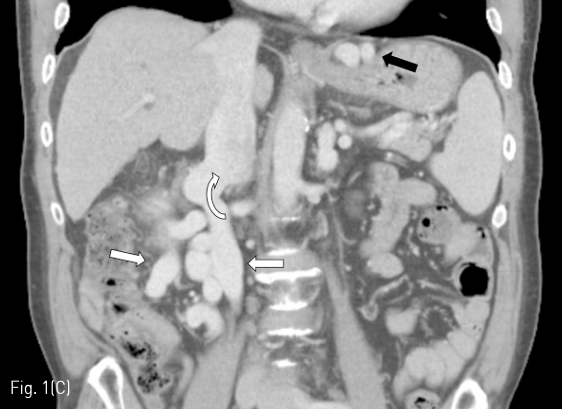

추적관찰

시술 2일 후 추적 검사로 시행한 dynamic liver CT에서 gastric and mesenteric-retroperitoneal varices의 complete thrombosis 소견을 확인할 수 있었다. 시술 후 CT에서 ascites가 새로 생겼으나 내과적으로 조절 가능한 수준이었다. 또한 SMV 내부에 partial thrombosis가 보였으나 임상적으로 문제가 되지는 않았다(Fig. 3A-C).

Fig 3A

(A-C) Contrast-enhanced CT images obtained 2 days after PARTO show complete thrombosis of gastric varices (black arrows) and mesenteric-retroperitoneal varices (white arrows). Arrow head indicates partial thrombosis of the SMV. White circles indicate plugs placed within the meso-caval shunt and the gastro-renal shunt.